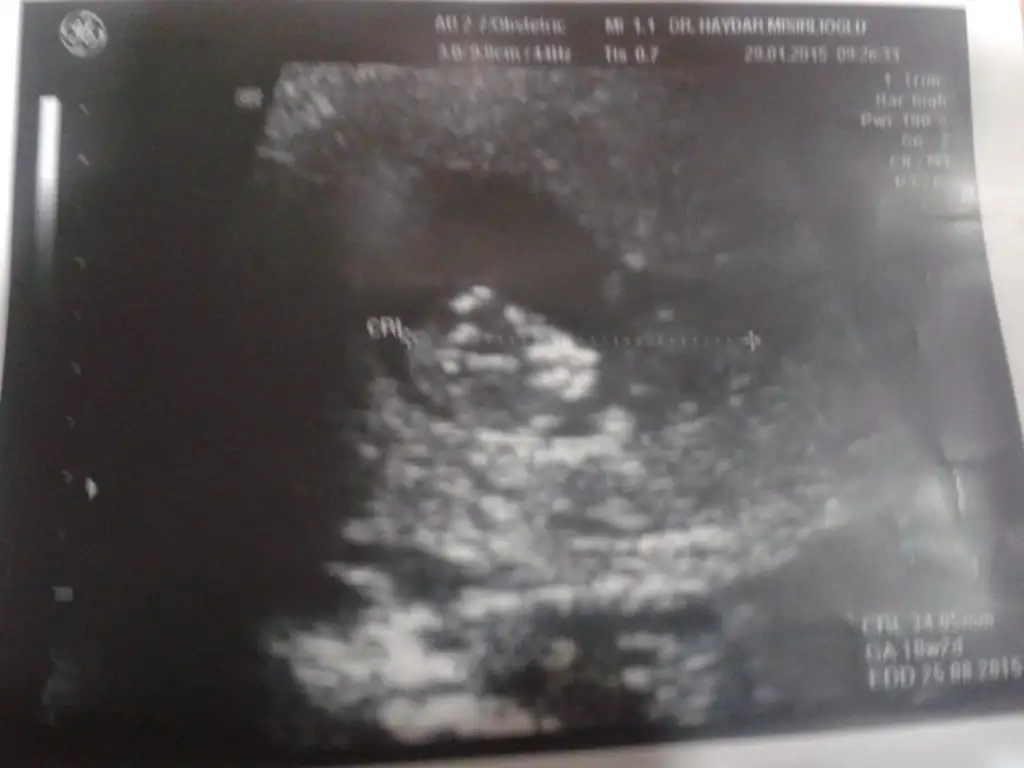

Bir oglum var bu ikinci lütfen anlayan arkadaşlar yorum yapın cokkkkk merak ediyorum.

Eklentiler

• 20150129_154951.webp

10,6 KB · Görüntüleme: 111

Merhaba arkadaşlar benim de bir oglum var bu ikinci gebeliğim benim bebişimin de cinsiyetine bi tahmin Söyler misiniz ?